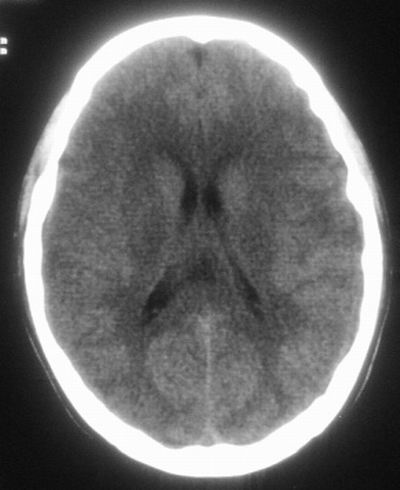

治疗三天后复查ct片示:

治疗三天后复查ct:除左侧额顶叶血肿外。左侧额叶另见片状低密度灶,密度不均匀,境界不清;考虑脑梗塞。

建议:必要时行进一步检查排除烟雾病。